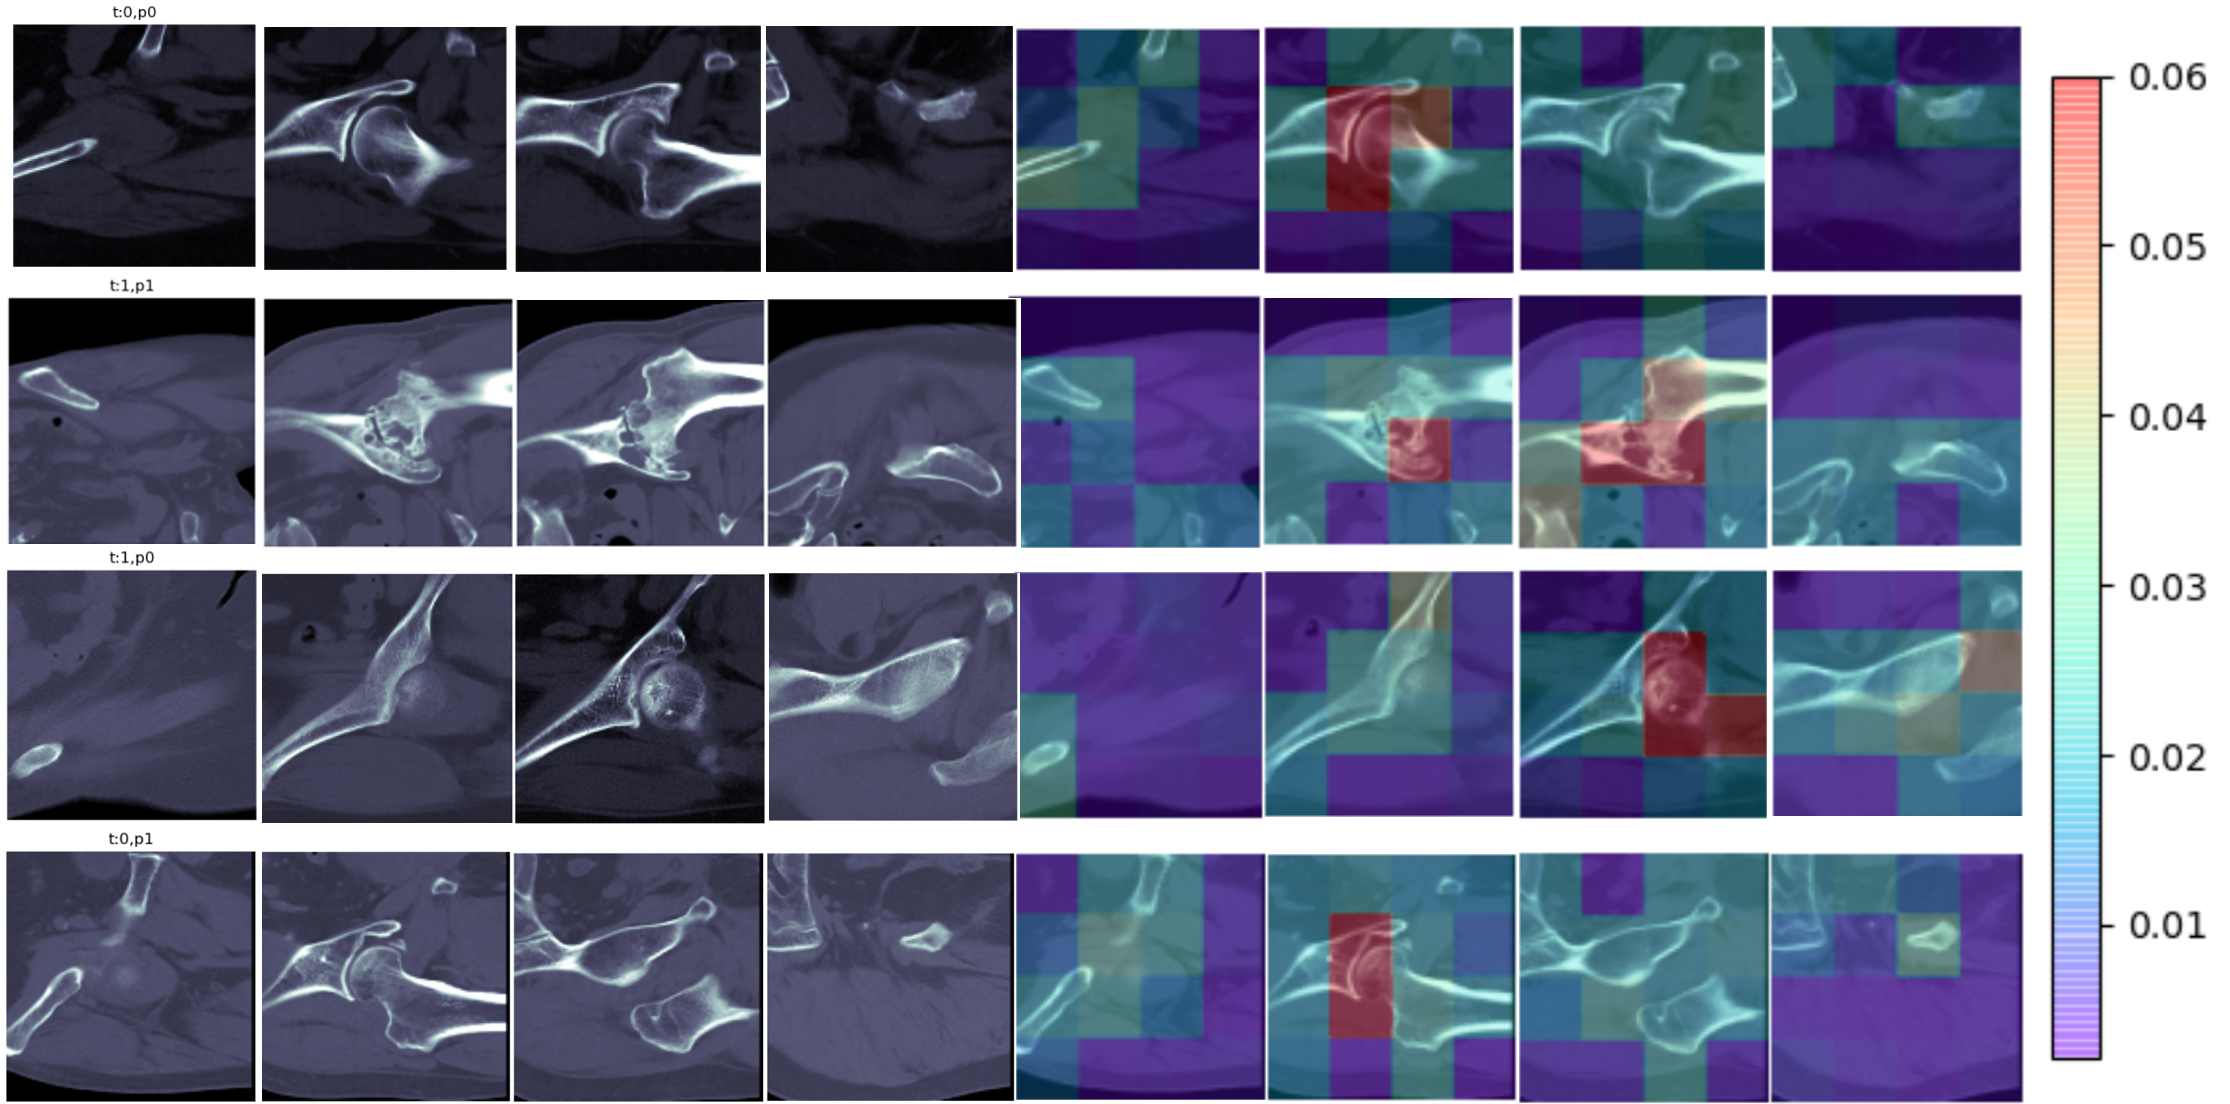

Refer to caption

Figure 5: Visualization of the patch attention map with structure regularized module. The first to fourth rows, respectively, are true negative cases, true positive cases, false negative cases and false positive cases. Each case is a randomly selected sample among that category. The left half of each row is the original CT image, and the right half is the corresponding patch attention map. The redder the patch in the patch attention map is, the greater the weight of the feature fusion, and the correspondence between the value of the weight and the color is reflected by the color bar on the right.

III-E Visualization of Patch Attention Map

There are some previous studies related to the diagnosis of AVNFH, and the data sets in these studies are both large and small, using X-ray and MR images. What they all have in common is the use of end-to-end neural networks, which allows the results predicted by the network to be used only as a reference by experts. However, our SRANet model can show the basis of model judgment by visualizing the patch attention map, which can assist the expert to speed up the diagnostic process and improve the rationality of the diagnostic process by focusing on the highlighted parts of the input CT images of the femoral head region. As shown in Fig. 5, the patch attention map in our SRANet model has a higher interpretability compared with other end-to-end benchmark model.